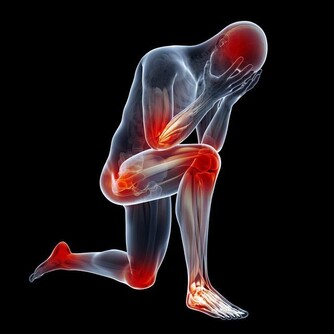

腿部拉筋,膝蓋不痛!

人老先老腿,腿上的筋結多了會引起很多的問題,我們在正常行走或在上下樓梯時,突然感覺膝關節吃不住勁,腿發軟,差點跪下,很多內科疾病也和腿上的筋結有關。

我們可以用手指在內外膝眼二個位置按揉,會發現手下有咕嚕咕嚕的感覺,膝關節過伸或勞累後疼痛,這就是膝蓋筋結。

把膝關節伸直看一看,如果膝眼是凹陷的,說明你的膝關節還可以,如果你的膝眼鼓起來了,摸到了硬硬的筋結,並且按著還有些疼,就說明膝關節退化的比較嚴重。

膝蓋有筋結,有問題光練膝蓋是不頂用的,股四頭肌是伸膝關節的力量來源,股四頭肌力量不夠,髕骨兩側就要出現筋結了,那時就不是打軟腿了,就該關節僵硬打不彎費勁了。所以說練好了這塊地方,膝蓋自然不疼。

緩解膝蓋筋結,我們可以做以下3個動作:

坐在椅子上,雙手合掌相對放在兩腿之間,雙腿盡量內收夾緊,雙手盡量外展,持續對抗10秒鐘;再將雙手放在大腿外側,雙腿外展,雙手內收持續對抗10秒鐘,重複20遍。

坐位,雙足跟交叉,下腿向前伸,上腿下壓,相互爭力堅持10秒,雙腿交替重複20遍。

可以到專業美容院讓美容師幫你按揉內外膝眼四個位置,會發現手下有咕嚕咕嚕的感覺,這就是在散筋結啦!